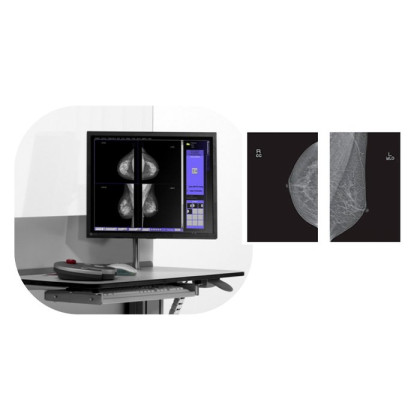

Маммограф Pinkview-AT (производитель Южная Корея) с аналоговой системой работы датчиков и электронной системой искусственного интеллекта собрал в себе все достоинства современных диагностических рентгеновских аппаратов.

Большой детектор плоскопанельного формата в сочетании с низкой долей излучения обеспечивает безопасность процедуры и высокую точность диагностики рака молочной железы. Качество и надежность прибора оценили многие специалисты.